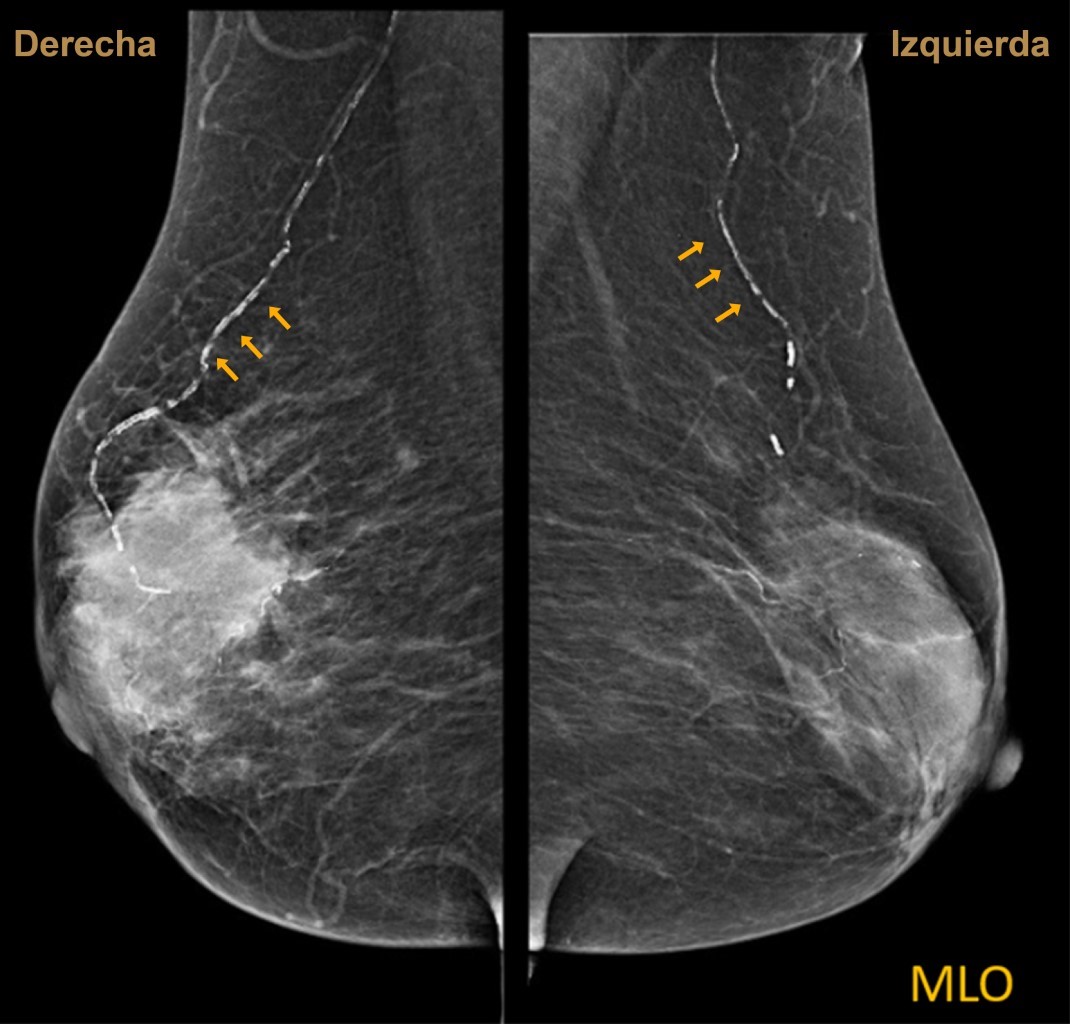

En la mastografía, estas calcificaciones suelen ser lineales y paralelas, en un patrón que se denomina "vía de ferrocarril", ya sean en forma focal o difusa.

Se trata de paciente femenino de 74 años con antecedente de diabetes mellitus tipo 2. Acude a mastografía de tamizaje. Se aprecian dos proyecciones, densidad mamaria tipo B, con un nódulo irregular hiperdenso de márgenes espiculados de 5.1 × 5.2 cm en sus ejes mayores y se aprecian calcificaciones lineales (Figuras 1 y 2). Se otorga categoría BI-RADS 5.

Figura 1